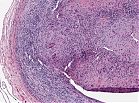

• Organdiagnose: Arterie (Querschnitt)

• fibrinoide Nekrose – im Bereich der Intima-Media-Grenze mit Zerstörung der Lamina elastica interna

• Granulationsgewebe

• entzündliches Infiltrat

• Riesenzellen, die sich an Bruchstücke der Elastica interna lagern

Abb. 457: Fibrinoide Nekrose mit Organisation und Zerstörung der Elastica interna